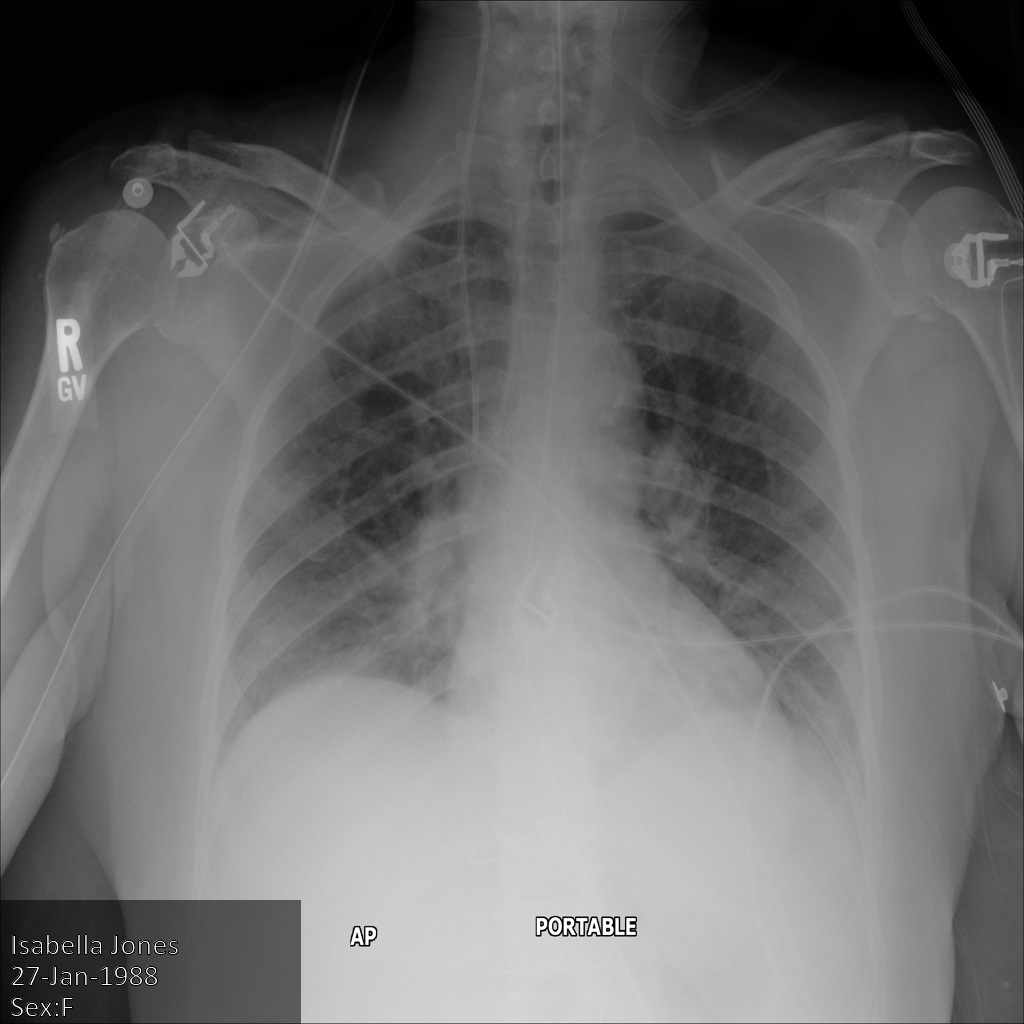

In der folgenden Abbildung sehen Sie eine nicht korrigierte Aufnahme eines Patienten:

Nachdem Sie das Bild mit der Option REDACT_SENSITIVE_TEXT an die Cloud Healthcare API gesendet haben, wird es wie folgt angezeigt:

Folgendes ist aufgetreten:

- Das

PERSON_NAMEunten links im Bild wurde entfernt. - Das

DATEunten links im Bild wurde entfernt.

Das Geschlecht des Patienten wurde nicht entfernt, da dies gemäß den Standard-DICOM-infos nicht als sensibler Text gilt.